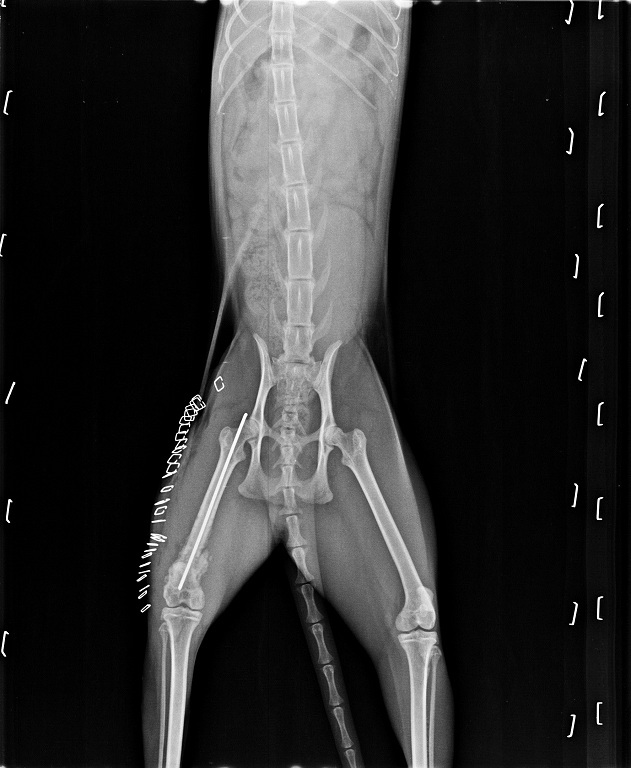

主題: 從高樓墜下嚴重骨折的小久- 後續住院治療、復健 申請者姓名: 臺北市支持流浪貓絕育計劃協會 花色: 申請日期: 2016-07-27 17:03:15 申請者部落格: 申請者臉書網址: 所在縣市/合作醫院: 台北市/其他院所醫助專案(醫院請先MAIL溝通) 治療費用: 69264元 需求人數: 73人 已結案 (2024-06-01 13:34:05) 報名人員: Samuel Peng Peng、彭壯雲(已付款)、Mia(已付款)、Lee Albert(已付款)、小U(已付款)、菲小比(已付款)、valen(已付款)、薇薇安(已付款)、吳璇(已付款)、aneta(已付款)、Mila Wang(已付款)、Chacha and Vivi(已付款)、Shan Chou x6(已付款)、李庭芝(已付款)、李庭芝 x2(已付款)、Miaow(已付款)、許瑞騰(已付款)、Scarlett x20(已付款)、小U、王佩于(已付款)、俋思國際有限公司(已付款)、micky(已付款)、Ginnie Gi(已付款)、Naommi(已付款)、許可可(已付款)、嘟嘟白白(已付款)、pai(已付款)、Celia(已付款)、小U、恩客(已付款)、貓婷(已付款)、Anne Chen(已付款)、Erin Lin(已付款)、泡泡(已付款)、Chin Fang Lai(已付款)、Wendy x2(已付款)、Jack Wei x6(已付款)、Ivy SU(已付款)、小U、Peter Pan x3(已付款)、howeer(已付款)、Una Chen、Una Chen(已付款)、Phoebe Wu(已付款)、iamjuliechang(已付款)、伊兒小舖 x3(已付款)、蘇小優(已付款)、Bella Hung(已付款)、凱倫 x2(已付款)、Ting Huang(已付款)、淼淼(已付款)、Jasmine Lin(已付款)、Jessica Pan(已付款)、王小盈(已付款)、coby0427 x2(已付款)、TC(已付款)、Yi-Ling Yao x2(已付款)、May May Lin(已付款)、攸yu x2(已付款)、 候補人員: 動物病情說明: 小久是一隻從高樓墜下受重傷的貓咪,

協會在接獲民眾通報之後,

志工即前往協助,

並帶著小久到重症醫療醫院進行治療。

小久剛住院時身上有著非常嚴重的傷勢和病症,

除了因從高樓墜下而導致前腳骨折之外,

嘴巴周圍的上顎和下巴都有劇烈的撞傷,

並且體內體外長著寄生蟲和黴菌,

也有血尿的問題......

幸好在經過醫生們的搶救之後,

福大命大的小久順利地完成手術,

但後續的療養照護仍是需要特別的注意。